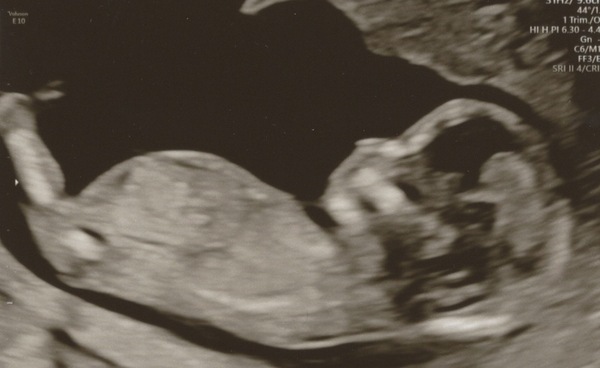

Ok I can't resist all this skull/nub theory talk. My husband really wants to be surprised so I am not going to intentionally find out/if I see anything I won't tell him, but I am very curious and thinking we are having a boy based on skull theory. Thoughts? This was our last scan at 13+3.

August 2021 - Heading into the second trimester

@WolfMother326 I’m pretty useless as this but I’ll guess boy too!

@WolfMother326 Yep from skull I’d say boy!

@WolfMother326 On the fence with your photo but I'm leaning towards a boy! What's your gut instinct? xx

@PurplePansy05 gut instinct is definitely boy (keep dreaming about him), but of course will be equally happy if we have a little girl!

@WolfMother326 I have no idea with these, but I think I’d guess boy!

@WolfMother326 this is the first I heard of the skull nub theory. I googled it but yes I think based on the 5 minute research it may be a boy. What are your thoughts?x